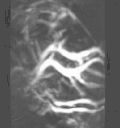

In order to capture sufficient thermoacoustic data to form an accurate 3D map of electromagnetic absorption, it is necessary to surround the anatomy being imaged with a 2D array of transducers. The world's first 3D thermoacoustic animal scanner (Fig. 8: left panel) accomplished this by combining a cylindrical array of 128 transducers (Fig. 8: center panel) with rotation of the animal being imaged about the vertical axis. The net result was to capture thermoacoustic data over the surface of a sphere surrounding the animal being imaged (Fig. 8: right panel).[21] This device was capable of visualizing structures as small as 1/3 millimeter. An animated 3D image of the vasculature in the head of a mouse is displayed in Fig. 9. This animated image was acquired using near infrared radiation at 800 nm, where optical absorption by blood is higher than surrounding tissues. Therefore, the vasculature is preferentially visualized.